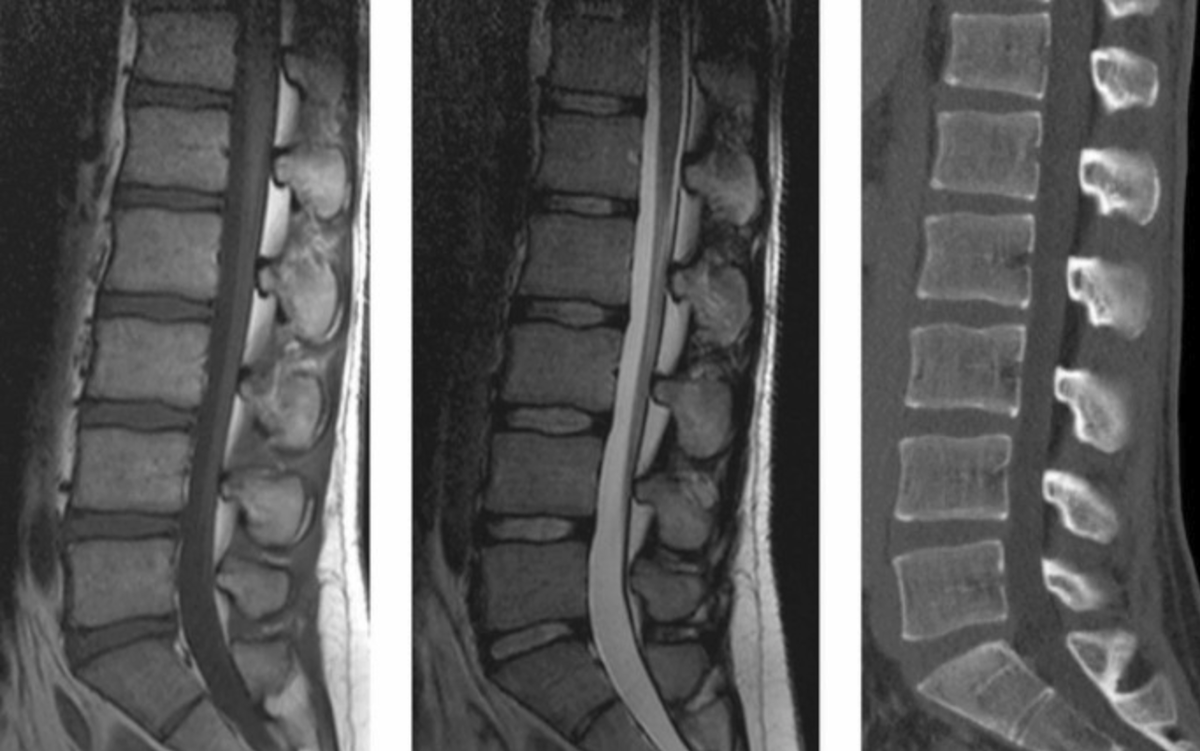

1 - МРТ, 2 - МРТ, 3 - КТ

✅ Патология спинного мозга (миелит, опухоли, компрессия корешков). КТ также будет скорее всего бесполезна. Обследование позвоночника на КТ обосновано когда мы ищем перелом / нам надо оценить костные структуры.